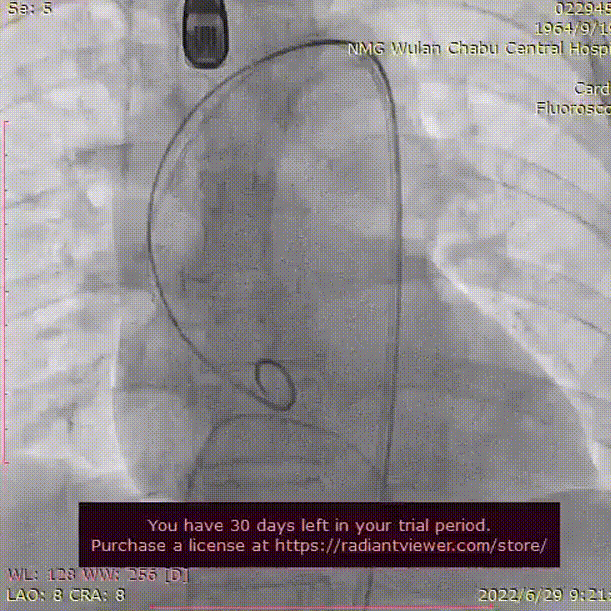

术中影像

主动脉根部造影

可见明显反流

导丝顺利跨瓣

瓣膜初始定位

瓣膜开花过程造影

工作位造影 位置良好

冠脉灌注良好

观察过程中瓣膜下滑

再次释放至工作位后

迅速释放

瓣膜形态良好 位置理想

微量瓣周漏 即刻跨瓣压差0mmHg